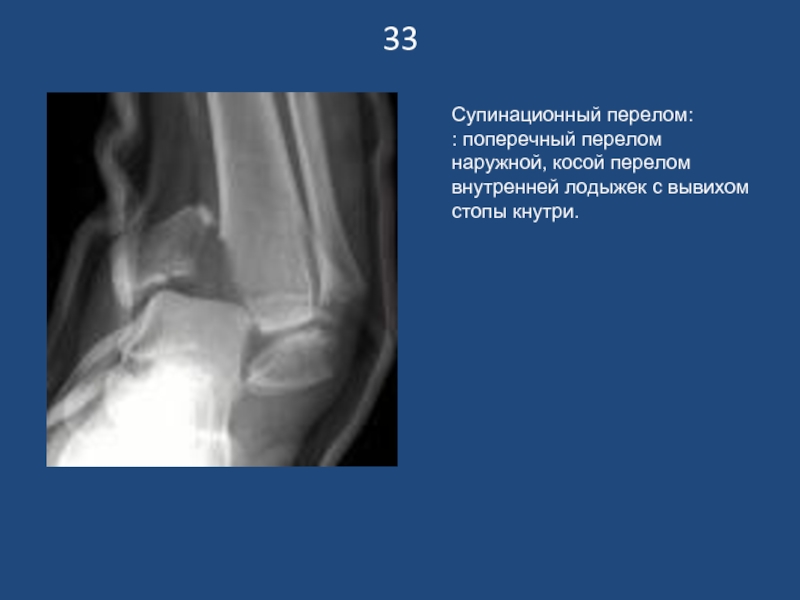

Слайд 3433

Супинационный перелом:

: поперечный перелом наружной, косой перелом внутренней лодыжек с вывихом

стопы кнутри.